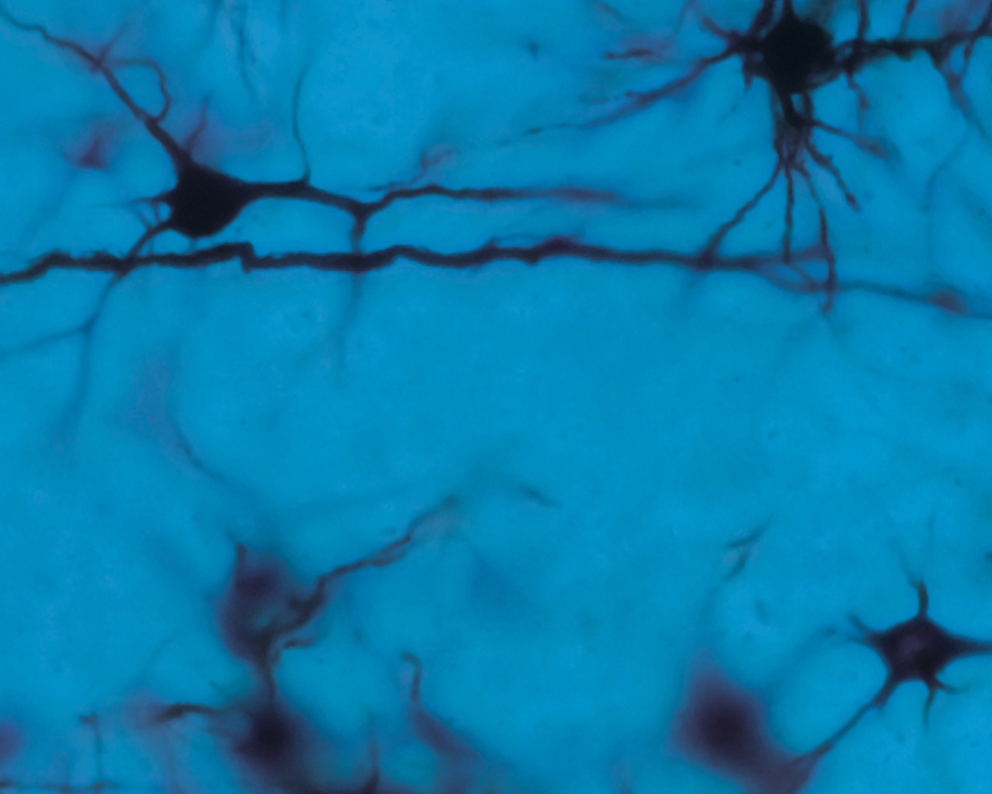

E se il cervello potesse controllare un dispositivo robotico esterno per permettere alle persone con lesioni del midollo spinale di recuperare alcune funzioni motorie?

Sono questi i risultati di decenni di ricerca guidati dal Professor Miguel Nicolelis, uno dei neuroscienziati più visionari del nostro tempo.

Dal Nicolelis Institute for Advanced Brain Studies, AASDAP, Brasile, Professore Emerito alla Duke University (USA) e Visiting Professor presso UniSR, Nicolelis è riconosciuto a livello internazionale per le sue ricerche pionieristiche sulle interfacce cervello–macchina (Brain–Machine Interfaces, BMI) — tecnologie che collegano il cervello umano a dispositivi esterni, aprendo nuove prospettive per le neuroscienze, la robotica e la neuroriabilitazione.

Durante la sua lectio, il Professore esplorerà come il cervello genera il movimento, come integra strumenti artificiali nel senso del sé e come le ricerche sulle BMI stiano ridefinendo il concetto stesso di recupero funzionale, a partire dai risultati straordinari del progetto Walk Again